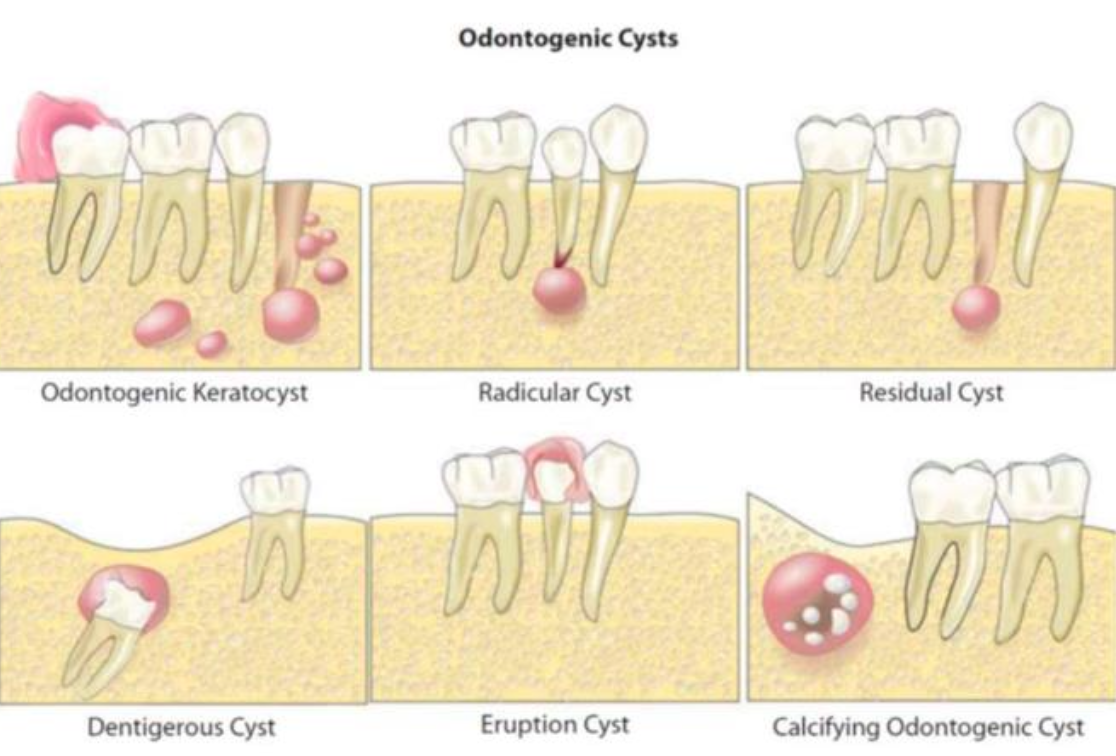

發育型

| 原因 | 好發 | 年齡 | 特徵 | ||

|---|---|---|---|---|---|

| Dentigerous cyst (DC) | follicle 分離 | 38,48 | 10 - 30y |

| Eruption cyst (EC) | Dentigerous 萌發 | 12a, 12b, 34a, ?6 | 10y ↓ | 藍色或紫棕色   |

| Odontogenic Keratocyst cyst (OKC) |

下顎骨後端,下齒槽管上方 | 10-40y | 組生齒(40%) | |

| Radiolucent、 MD方向下顎骨吸收,但牙根完整。  |

| 4-8 層、副角化(有核)、Basal cell 為 palisaded(柵狀) | |||||

| 高復發 (30%) | |||||

Orthokeratinized Odontogenic cyst (OOC) |

- | 下顎後牙 | 年輕人 | 阻生齒 (66%)、 granule layer 明顯 、 生長慢 |

| Gingival Cyst of the newborn | dental lamina rest | 新生兒上顎牙齦  |

- | 管腔內含有角質碎屑(keratinaceous debris)  |

| Gingival Cyst of the adult (LPC 長出來) | 下顎premolar、canine facial 牙齦 | 40-60y | 藍色(bluish)、藍灰色(DeepSkyBlue-gray)  |

| focal plaques | |||||

focal plaques |

| Lateral Periodontal (LPC) | 下顎 premolar、canine、lateral incisor lateral root 表面 | 40-70y | |||

類似 OKC,但推開牙齒  |

| Botryoid Odontogenic Cyst (BOC) | 多囊 LPC | ||||

| Calcifying Odontogenic Cyst ( Gorlin Cyst, COC) |

- | 前牙(65%)  |

20-40y 若有 odontoma,17y 發病 |

未萌發的牙齒(33%)、 阻生齒(66%) | |

basal cell reverse polarity  |

ghost cells (嗜酸無核)  |

| β catenine + | |||||

| Peripheral Calcifying Odontogenic Cyst | COC 長出來 | - | 60-80y | . |

| Glandular Odontogenic Cyst (GOC) | - | 下顎前牙 | 46-51y | 跨中線、無 MAML2 | |

復發、局部侵犯性,吃 cortical bone  |

| 杯狀細胞, cilia, focal plaques | |||||